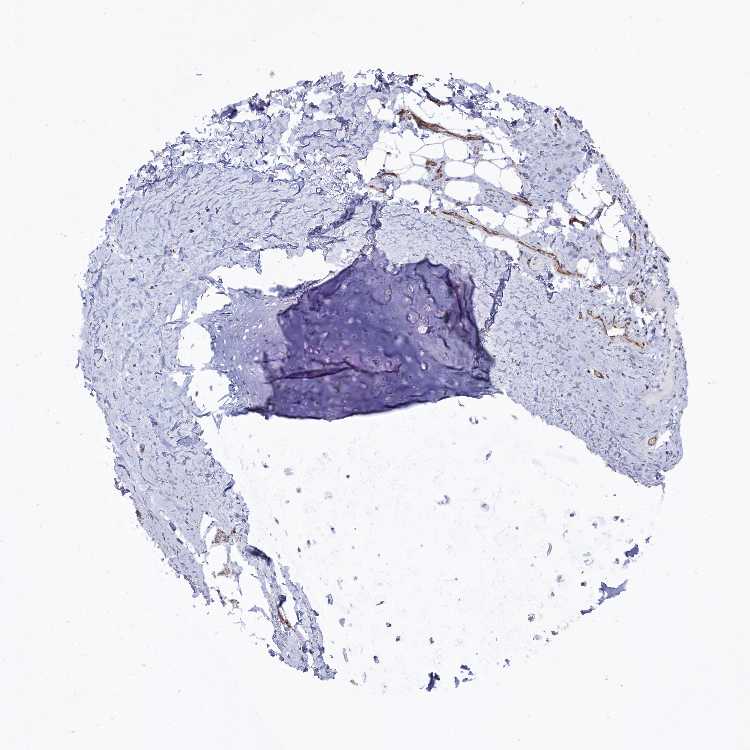

ADIPOSE TISSUE - Antibody stainingi

Antibody staining in the annotated cell types in the current human tissue is reported as not detected, low, medium, or high, based on conventional immunohistochemistry profiling in selected tissues. This score is based on the combination of the staining intensity and fraction of stained cells.

Each image is clickable and will lead to virtual microscopy that enables deeper exploration of all samples and also displays staining intensity scores, fraction scores and subcellular localization as well as patient and tissue information for each sample.

Antibody HPA042767Antibody HPA042835

Adipocytes Not detectedNot detected